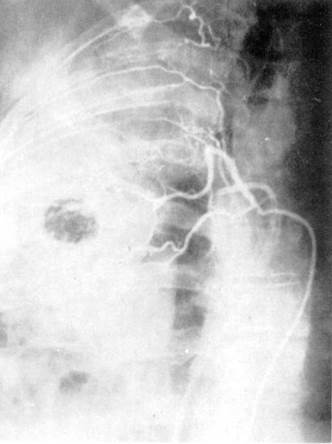

Бронхиальную артериографию

в регионах выше и ниже выявляемых анастомозов двух систем кровообращения легких. Рис. 6.

Ангиопульмонография.

а — артериальная фаза; б — капиллярная фаза; в — венозная фаза.

Селективная ангиография бронхиальных артерий.

При анализе ангиопульмонограмм

обращают внимание на пофазовое

продвижение контрастного вещества по различным регионам легкого: легочной артерии, капиллярного русла, венозной системы малого круга кровообращения (рис. 6).

Сериография,

проводимая, как правило, в переднезадней проекции, может быть дополнена рентгенограммами в боковой или косой проекциях в зависимости от задач исследования (рис. 7).